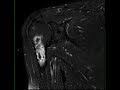

Bone Infarct Humerus

58-year-old male who presents for chronic right shoulder pain. There is an infiltrative T1 hypointense, STIR heterogeneously hyperintense lesion centered within the proximal right humeral diaphysis with extension to involve the metaphysis. There is heterogeneous enhancement. There are central components of the lesion which are both T1 hyperintense and STIR hypo-intense compatible with internal fat. The lesion is centered within the medullary cavity without definite endosteal scalloping, cortical breakthrough, or associated soft tissue component. Imaging findings are most compatible with bone infarction. Bone infarct is secondary to interruption of blood supply to bone. A central necrotic core is established with a hypoxic peripheral zone. Causes include trauma, Caisson disease, hemoglobinopathy, radiation therapy, connective tissue disorders, steroid use, pancreatitis and alcohol use.